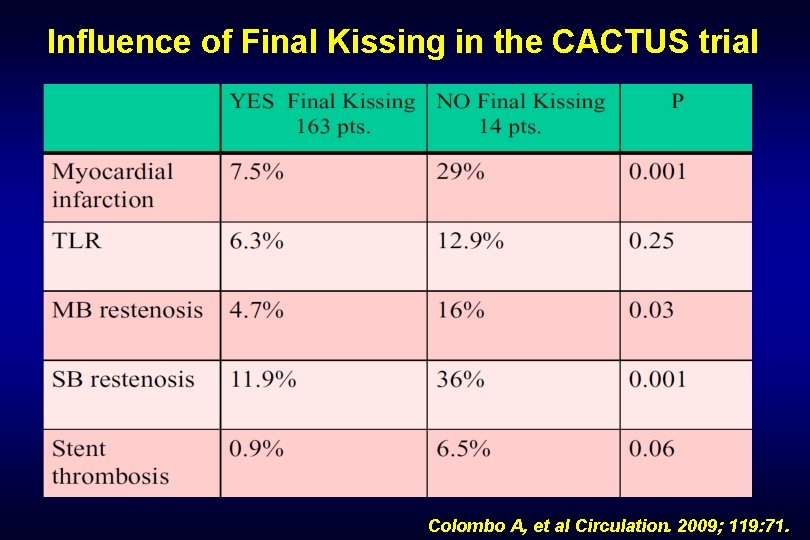

Influence of Final Kissing in the CACTUS trial Colombo A, et al Circulation. 2009; 119: 71.